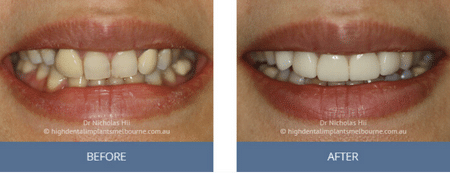

Clinical Before and After Photos

At High Dental, we believe a great smile changes everything. Our Smile Gallery showcases before-and-after images of patients who trusted us with their smiles. From veneers and crowns to full-arch implants, each result is unique — and each started with a consultation. Scroll through and imagine the possibilities for your own smile.

Images are provided for illustrative purposes only. Results shown relate to specific patients and individual outcomes may vary. A consultation is required to determine suitability for treatment.